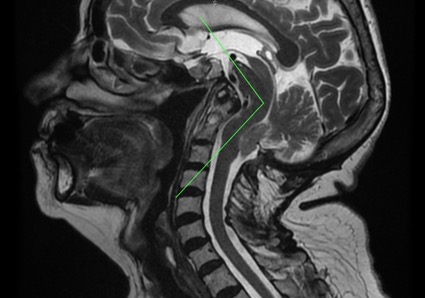

Fig.2- RM Cranio-cervicale sagittale con Inversione del Processo dell’Odontoide. Oltre a questo si rileva: Invaginazione basilare, Abbassamento delle tonsille cerebellari, Kinking del tronco cerebrale. Si noti l’aumento dello spazio sopra-cerebellare, evidenza a favore della teoria della trazione e contraria a quella malformativa da riduzione della fossa posteriore.

La diagnosi di Inversione del Processo dell’Odontoide è radiologica, si può effettuare mediante TAC (Fig.1) o RM (Fig.2) del cranio o dell’encefalo e della colonna vertebrale o del midollo spinale cervicale.

La sua diagnosi si determina tracciando la linea di Thiébaut-Wackenheim-Vrousos, che è il proseguimento verso il basso del piano della base: l’apofisi odontoide dell’asse deve rimanere di norma tangenziale, o la separazione da questa linea non deve superare i due millimetri.